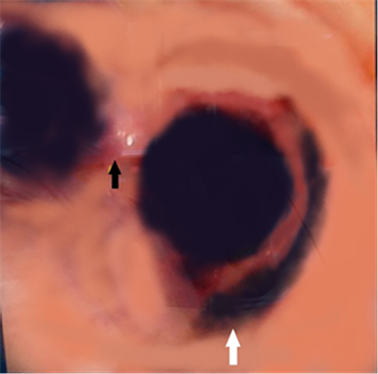

纤支镜下可观察到在隆突两侧各有一支气管开口,隆突上方右侧有一右肺上叶气管开口,考虑为TB(见图1)。查看患者术前CT示:在CT图像165(image,im165)可见右肺上叶开口于主气道(见图2),在im182可见正常的左右主支气管开口于主气道(见图3),证实该患者为TB。

2.jpg

图2 CT,im165,黑色箭头:异常的右肺上叶开口